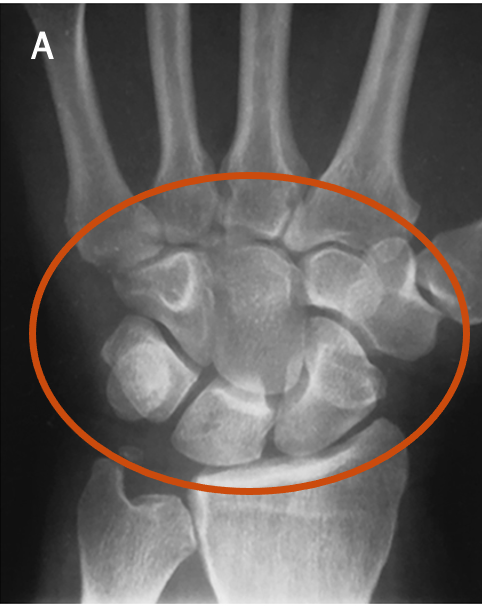

What type of bones are circled in figure A? How many carpals are there?

A

Short bones

8 carpals

Q

What pathology does this projection demonstrate?

Demonstrates abnormal calcifications and bony changes in the carpal sulcus that may impinge on the median nerve